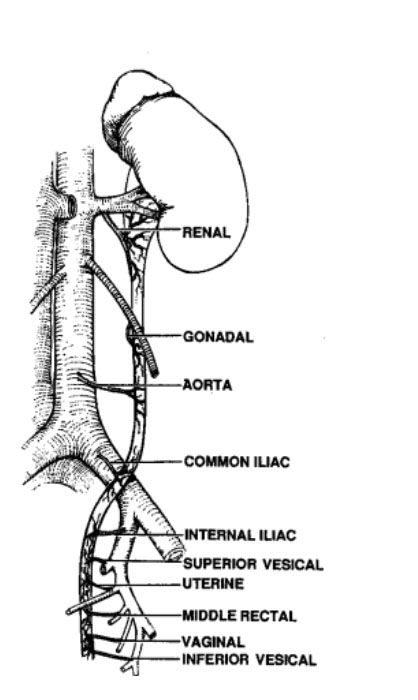

如下图所示,沿输尿管走行,其接受多支动脉血供(如下图所示),在腹膜后,依次为肾动脉、生殖动脉、腹主动脉和髂总动脉。进入盆腔后,远端输尿管的血液供应包括髂内动脉或其分支,尤其是膀胱和子宫动脉,还有直肠中动脉和阴道动脉等。这些分支到达输尿管后,分布在筋膜层并上下沟通,形成动脉网,然后再散布到其他各层。因输尿管的血供具有广泛的交通支,所以可以安全的适当范围游离输尿管而不会导致输尿管坏死。

The sources of arterial blood supply to the ureter